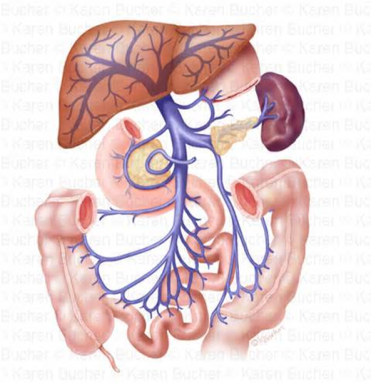

“Reflüks” ileit nədir?

Xoralı kolitdə terminal ileumun orta dərəcədə iltihaba cəlb olunması. İltihab mediatorlarının kolondan terminal ileuma qayıtması nəticəsində meydana gəlir.